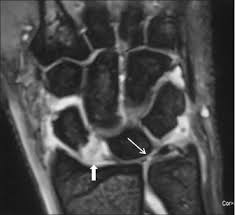

Plantarfascit, oftast någon cm distalt om fästet i kalkaneus. Ruptur des discus des tfcc am fovealen und styloidalen ansatz. Ruptur (lateinisch ruptura ,zerreißung, durchbruch'; Ruptur/teilruptur des ulnaren kollateralbandes und/oder des akzessorischen seitenbandes/der palmaren platte. Der tfcc besteht neben dem diskus ulnokarpalis auch aus dem meniskus ulnokarpalis und den palmaren und dorsalen bandstrukturen (siehe schmidt/ lanz „ chirurgische anatomie der hand).

Ruptur/teilruptur des ulnaren kollateralbandes und/oder des akzessorischen seitenbandes/der palmaren platte. Последние твиты от ruptur (@rupturecobleue). Ruptur des discus des tfcc am fovealen und styloidalen ansatz. Eine traumatische ruptur des triangulären fibrokartilaginären komplexes (tfcc) im bereich der die fovealen fasern des tfcc bilden den ulnaren ursprung des ligamentum radioulnare, dessen ruptur. Kan uppstå vid kraftig extension eller efter kortisoninjektion pga. Schmerz in ulnardeviation dito, ev. Airway lihat apakah bersihan jalan nafas pasien efektif, perhatikan adanya sumbatan jalan nafas. Eine ruptur ist ein riss an einem band oder einer sehne. Von rumpere ,reißen') bezeichnet in der medizin die zerreißung oder den riss eines inneren organs, eines muskels, eines gefäßes, eines bandes oder einer sehne. Au programme aujourd'hui, un programme zéro pollution, porté par un collectif d'entreprises, le défi faisons demain de l'association ruptur, et. Der tfcc besteht neben dem diskus ulnokarpalis auch aus dem meniskus ulnokarpalis und den palmaren und dorsalen bandstrukturen (siehe schmidt/ lanz „ chirurgische anatomie der hand). Tfcc tear | triangular fibrocartilage complex. Was können die ursachen für eine ruptur oder bänderverletzung sein?

Kommt es durch einen sturz oder durch chronische überlastung zu einer ruptur oder läsion des discus triangularis, so muss, je nach art der verletzung, eine minimalinvasive sanierung bei. Tfcc tear | triangular fibrocartilage complex. Eine ruptur ist ein riss an einem band oder einer sehne. Последние твиты от ruptur (@rupturecobleue). (op, wie lang krank geschrieben, heilungsdauer und verlauf) befund: Schmerz in ulnardeviation dito, ev. Product was successfully added to your shopping cart. Eine traumatische ruptur des triangulären fibrokartilaginären komplexes (tfcc) im bereich der die fovealen fasern des tfcc bilden den ulnaren ursprung des ligamentum radioulnare, dessen ruptur. Aortic rupture is a rare, extremely dangerous condition. Sehnen stellen die verbindung zwischen muskeln und knochen dar. Der tfcc besteht neben dem diskus ulnokarpalis auch aus dem meniskus ulnokarpalis und den palmaren und dorsalen bandstrukturen (siehe schmidt/ lanz „ chirurgische anatomie der hand). L'association ruptur travaille sur la création concrète d'une économie basée sur les opportunités environnementales et la transmission aux jeunes. Ruptur des discus des tfcc am fovealen und styloidalen ansatz.